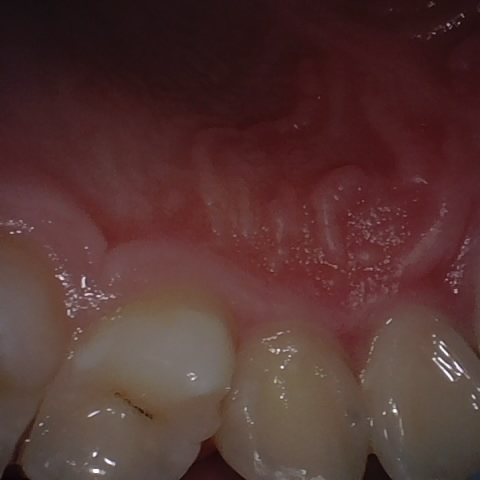

Annotated as "Good"